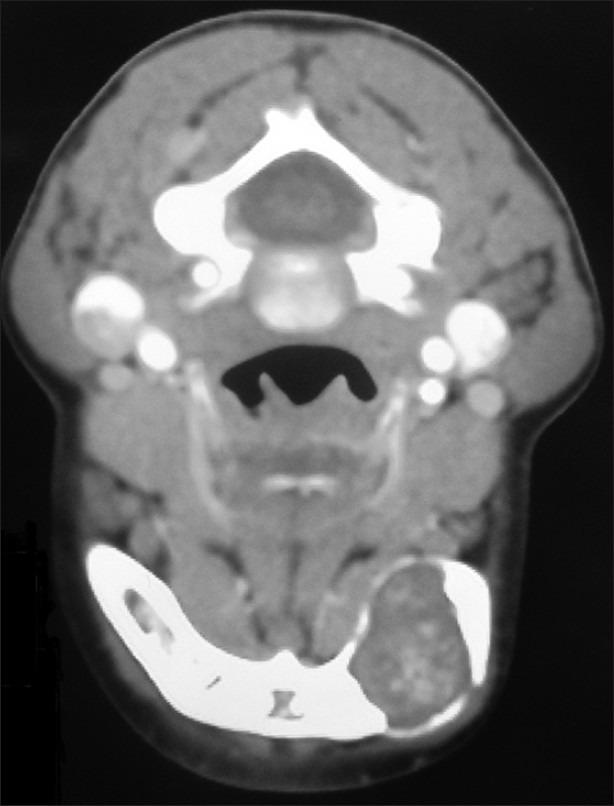

Intraosseous schwannomas is a very rare neoplasm, and less than 50 cases have been reported in the medical literature. In this article, the clinical, radiographic and histopathologic appearances of a rare case of intraosseous schwannomas are presented. The importance of this case is that other benign central lesions such as odontogenic tumors and cysts might be included in differential diagnosis. This case was recognized in a 9-year-old child, which is a very rare occurrence. The diagnosis was confirmed by immunohistochemical staining with S100 protein.

骨内施万细胞瘤是一种非常罕见的肿瘤,医学文献中报道的病例不足50例。本文介绍了一例罕见的骨内施万细胞瘤的临床、影像学和组织病理学表现。该病例的重要性在于,在鉴别诊断中可能需要考虑其他良性中心性病变,如牙源性肿瘤和囊肿。该病例发生在一名9岁儿童身上,极为罕见。通过S100蛋白免疫组化染色确诊。